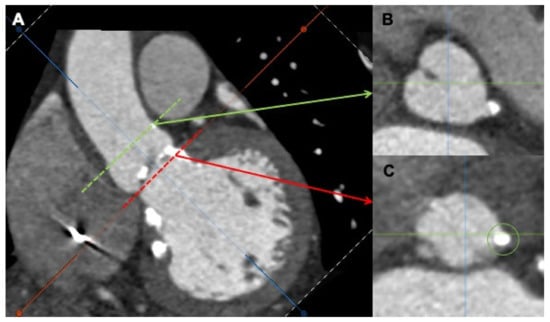

Figure 4.

Multidetector computed tomography angiography (MDCTA) showing severe calcification at the level of the left coronary cusp (A). Transversal views at the left coronary artery (B), green arrow and the aortic ring (C), red arrow.